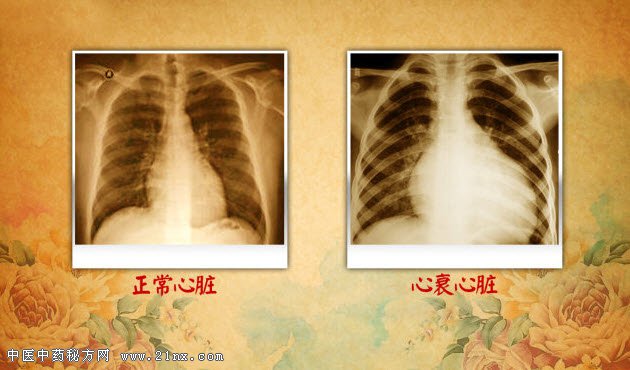

图:正常心脏和心衰心脏 身体里那只危险的“蝴蝶”,位于气管的前方。如果是比较瘦的观众,可以尝试自己摸一下。手指放在气管中下部,咽口口水,质地较韧的就是。它是人体最大的内分泌腺体,它是人体代谢和发育的主要调控者。它们能够增加人体的代谢、促进生长发育、提高神经系统和心血管的兴奋性等。因为心脏是这种激素重要的作用靶器官,并通过直接或间接的作用影响心率和心肌收缩力。要说它与心脏病的关系,可以说非常“暧昧”。打个比方,它是心血管系统的“司令部”,它下达命令,心脏就要执行。它到底是什么器官?扫描并关注养生堂微信公众号,答案在等着您。 老年人和女性是这种疾病的高发人群。一半以上的患者不知晓自己的病情,或者症状很轻,常误认为抑郁或更年期的症状。没有及时治疗,后果可以很严重。中华医学会内分泌分会于2010 年公布的“中国十城市社区居民疾病流行病学调查”结果,在被调查的15181 例中国城市人群中,它的患病率是6.5%。到底它是哪个器官,会对心脏造成什么影响呢?敬请关注本期《养生堂》为您带来的《揭开迷雾保心脏》。